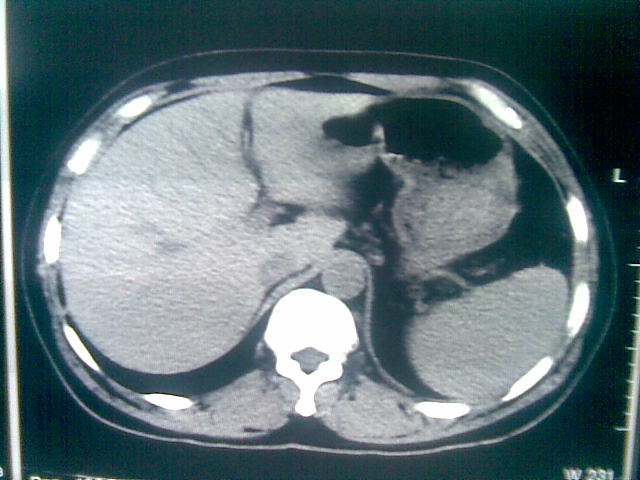

标题: CT23981:男,38岁阑尾炎术后透视胸腔积夜!做CT如下!积液包 [打印本页]

标题: CT23981:男,38岁阑尾炎术后透视胸腔积夜!做CT如下!积液包

可能与阑尾术后关系不太大,1.胸膜增厚粘连见少量气体。包裹脓气胸?左侧网膜囊脓肿?

.胸膜增厚粘连见少量气体。包裹脓气胸

左侧胸膜增厚、粘连+包裹液气胸。